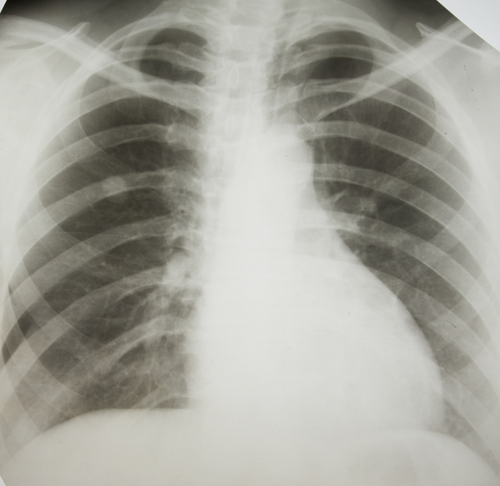

HAVANA, Cuba — Researchers from Cuba's Center of Molecular Immunology have developed a vaccine that is capable of reigning in late-stage lung cancer — turning what was almost certain death into a manageable chronic illness.

The new vaccine, CimaVax-EGF, works by getting the body to create antibodies against the epidermal growth factor receptor, a protein related to all cell growth, but which works unchecked in certain types of cancer, including lung cancer.

The vaccine is not meant for preventing lung cancer, but rather for keeping it in check over the long term after other treatments have failed.

Lung cancer kills more people in the U.S. than any other form of the disease — around 158,000 in 2007, according t the CDC. It is also one of the most preventable — about 90 percent of cancers that originate in the lungs are caused by smoking.